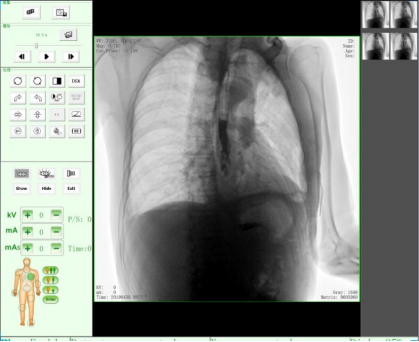

胸片

隨著人們健康意識不斷提高,越來越多人重視健康體檢,而數字化DR拍片幾乎是體檢必檢項目之一,胸片結果正常DR報告顯示為:胸廓對稱,兩側肋骨、肋間隙正常;兩肺紋理清晰,未見明顯實質性浸潤;兩側肺門和縱隔影來見明顯異常;心臟大小、形態在正常范圍內;膈肌平滑,雙側肋膈角銳利時,則說明您一切正常。那么,數字化DR胸片報告不正常的結果有哪些呢?

肺紋理是由肺動脈、肺靜脈以及淋巴管所組成,在肺里呈現白色,觀察肺紋理應注意它的多少、粗細、分布,以及有無扭曲變形等。它的改變受多種因素影響,如咳嗽、吸煙等都會造成肺紋理的增多、增粗,這并無典型的臨床意義。需要隨訪,前后胸片的對照,并密切結合臨床進行分析,尤其是對多種心肺疾病的診斷有著重要意義和參考價值。

這就是在肺里該黑的地方變白了,它是由于急性炎癥的滲出所致,當肺部急性炎癥進展到某一階段時,肺泡內氣體即被由血管滲出的液體、蛋白及細胞所代替,形成滲出性實變。而這種實變取代了原先肺泡內的氣體,從而擋住了X線,致使在數字化DR片上呈現出一片白色陰影。

老慢支,肺氣腫,肺心病,這時您的數字化DR片可能會呈現這種胸片,當進一步發展時,將會出現兩肺透亮度增加。由于肺泡過度通氣致使X光胸片上黑化度增加,即越黑透亮度越大。哮喘發作時同樣可見兩肺透亮度增加,呈過度充氣狀態。當然,X線攝影條件過高或是顯影時間過長也會導致這樣。

如果臨床表現為在原有咳嗽、咳痰的基礎上有逐漸加重的呼吸困難,甚至有胸悶、氣急、桶狀胸。常見的嚴重肺氣腫、肺大泡還會導致氣胸,也就是胸腔內的氣體將肺壓縮,使被壓縮的肺與胸壁間出現透明的含氣區,其中不見肺紋理。這些多是由白變黑的異常。